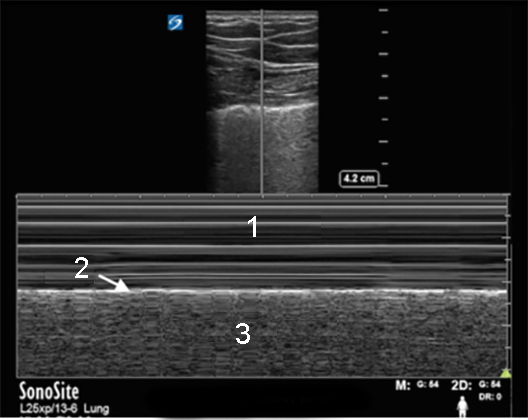

RUSH Lung Linear Sea Shore Sign Image

Waves in the Sea

Pleura

Sands on the Shore